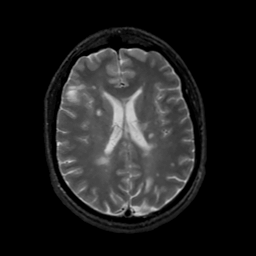

MR Study #7, March 24, 1991 -- Slice #30